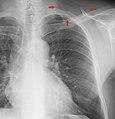

Projectionally rendered CT scan, showing the transition of thoracic structures between the anteroposterior and lateral view